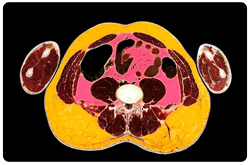

La obesidad abdominal es reconocida como un fuerte predictor de los desórdenes metabólicos asociados con la obesidad. El exceso en la acumulación visceral de grasa, también conocido como obesidad intra-abdominal o visceral, está fuerte e independientemente asociado con la alteración metabólica como la resistencia a la insulina, hipertensión y dislipidemia, los cuales son importantes factores de riesgo para la enfermedad cardiovascular. Se ha encontrado que características específicas de los depósitos de tejido adiposo visceral, que incluye grasa omental, mesentérica y retroperitoneal, están relacionados con o llevan a alteraciones metabólicas.